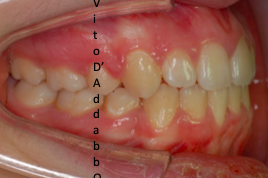

prima

dopo – fase 1